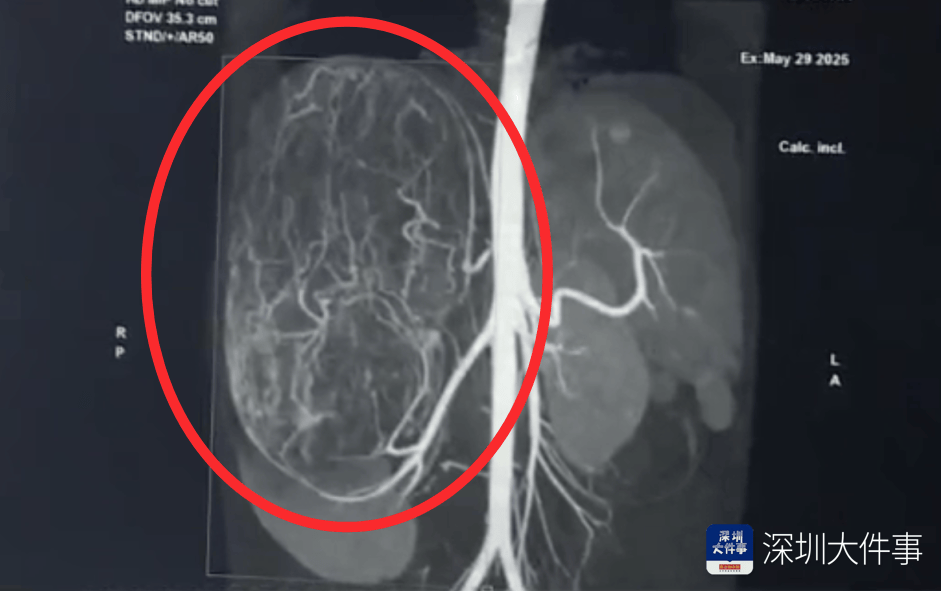

影像检查结果出来,所有人都倒吸一口冷气:一个直径27厘米(比篮球还大)的巨型肿瘤,霸占了整个腹腔右半边豌豆币。肝脏被它硬生生挤到了肚脐眼以下的位置!

肿瘤体积过大,这也意味着留给医生的手术空间实在有限,强行微创?万一瘤子破了,肿瘤扩散大出血,后果不堪设想!所以,只能通过开放手术来做豌豆币。

5月30日,医生为婷婷做手术,打开腹腔后,医生遇到了挑战:婷婷的肾动脉异于常人:正常人就1根肾动脉供血,她居然有3根豌豆币。还有一支来自腹腔干动脉,一支来自腰动脉。

这三根“命脉”就盘踞在巨大的瘤体上,稍有不慎,剪错一根,就可能引发大出血豌豆币。

手术团队屏气凝神,抽丝剥茧,一根一根精准找到、小心分离、稳稳阻断……经过3个多小时的精密操作:重达2.43公斤直径达27厘米的“巨无霸”肿瘤被完整端出豌豆币。周围需要清扫的淋巴和脂肪组织也被清除。